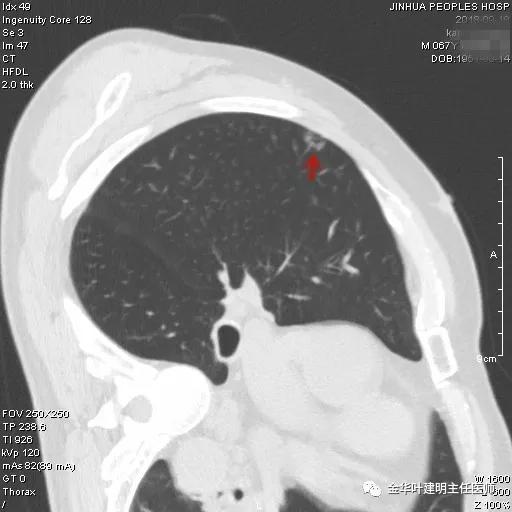

靶扫描以后还发现上叶另外地方还有一磨玻璃结节,约1厘米左右,密度较淡,但瘤肺边界清楚,也是较为典型的腺癌影像:

如此,右上肺是多发磨玻璃结节,考虑多原发癌。按病灶大小及所处部位,需要行右肺上叶切除,并淋巴结采样或清扫。鉴于其存在肺部炎症情况,建议其先抗炎治疗7-10天,待咳嗽、咳痰症状不明显,血象及C-反应蛋白等均正常后再考虑行胸腔镜下微创手术,因为合并肺部炎症情况下手术,术后呼吸道并发症发生率增高,也容易出现肺不张、支气管胸膜瘘或低氧血症等相关风险。